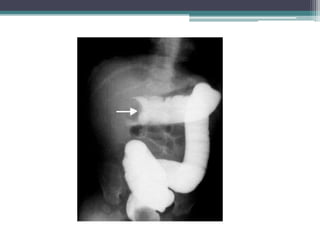

Tài liệu bàn về tắc ruột, bao gồm định nghĩa, phân loại và nguyên nhân của tình trạng này, với sự phân biệt giữa tắc cơ học và cơ năng. Các triệu chứng và chẩn đoán lâm sàng được trình bày, kèm theo phương pháp chẩn đoán cận lâm sàng như x-quang và siêu âm. Ngoài ra, tài liệu cũng đề cập đến các biến chứng và hậu quả của tắc ruột.